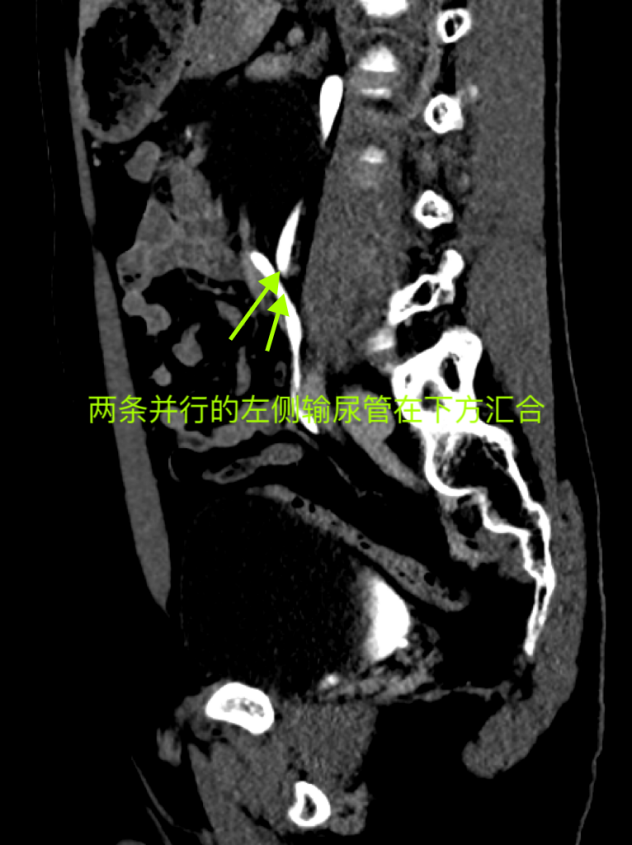

在聽完岳峰主任詳盡的解釋后,陳先生迅速辦理了入院手續(xù),并進一步完善了泌尿系CTU及腎CTA+CTV檢查。檢查結(jié)果果然顯示,陳先生左側(cè)存在重復(fù)腎及重復(fù)輸尿管,并且更為罕見的是下位重復(fù)腎伴有重度擴張積水。

術(shù)前腎CTA+CTV影像

術(shù)前CTU矢狀位影像